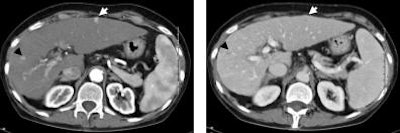

| In the hepatic arterial phase (left), a hypervascularized hepatocellular carcinoma lesion in the right liver lobe segment 7/8 (black arrow) and a second in the left liver lobe were clearly depicted. Venous-phase imaging (right) showed a decrease of signal in the small node in segment 7/8 (black arrow) and isodense contrast of the second lesion in segment 3 (white arrow). Using contrast-enhanced (Iomeprol 400 IV) MDCT, the HCC nodule (white arrow) was best seen in arterial phase, whereas the venous phase missed the lesion. Images courtesy of Dr. Renate Hammerstingl. |